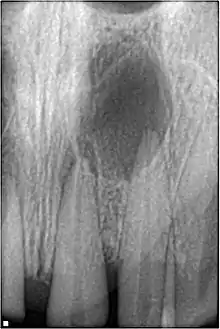

Pulpal necrosis

Pulp necrosis usually occurs either as ischaemic necrosis (infarction) caused by disruption to the blood supply at the apical foramen or as an infection-related liquefactive necrosis following dental trauma (2). Signs of pulpal necrosis include[40]

- Persistent grey colour to tooth that does not fade

- Radiographic signs of periapical inflammation

- Clinical signs of infection: tenderness, sinus, suppuration, swelling

Treatment options will be extraction for the primary tooth. For the permanent tooth, endodontic treatment can be considered.

Pulpal obliteration

4-24% of traumatized teeth will have some degrees of pulpal obliteration that is characterized by the loss of pulpal space radiographically and yellow discolouration of the clinical crown. No treatment is needed if it is asymptomatic. Treatment options will be extraction for symptomatic primary tooth. For symptomatic permanent tooth, root canal treatment is often challenging due to pulp chamber is filled with calcified material and the ‘drop off’ sensation of entering a pulp chamber will not occur.[42]